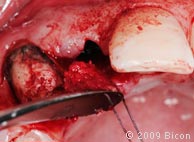

12. Расщепление костной ткани с помощью расширяющего долота 5,5 мм в области верхнего левого бокового резца.

13. Расширение лунки с помощью голубой ручной фрезы размером 3,5 мм, закрепленной на прямом держателе.

14. Костная ткань, собранная в лопасть 3,5 мм фрезы.